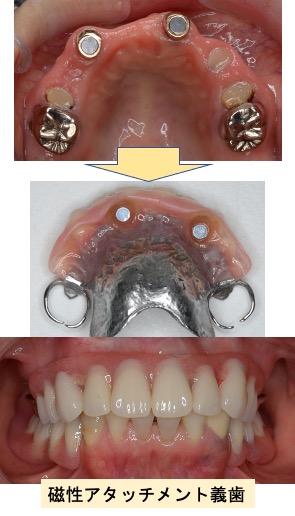

入れ歯(有床義歯)治療

むし歯や歯周病などが原因で、歯を失った場合の治療です。たくさん歯が残っている場合には、ブリッジによる治療が機能性・審美性に優れ、違和感も少ないのですが、ブリッジの支えになる歯が丈夫でなかったり、失った歯の本数が多い場合には入れ歯による治療が適応になります。入れ歯は材質やデザインによって見た目や装着感が大きく異なります。個々の患者さんに合わせた入れ歯を作製いたします。